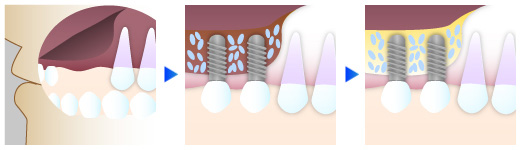

④ 骨が足りない患者様でもインプラント治療を可能に

インプラント治療では、埋入するために必要な顎の骨が足りない場合に、手術を行えない事も良くあります。当院では、骨が足りない患者様にもインプラント治療をご提供するために、骨造成を行って、インプラント治療を可能にしています。当院が、実施する骨造成法をご紹介致します。

サイナスリフト

上顎にインプラントを埋入する際に、骨の厚みが5mm以下とほとんど骨が残っていない場合には、切開した上顎洞に直接人工骨を置き、骨を再生して厚みを得る方法を行います。

GBR法(骨再生誘導法)

インプラント体を埋める骨の厚みを得るために、骨の元となる骨補填剤を保護膜(歯茎の混入防止)で覆って、骨の再生を促します。個人差もありますが、およそ4~5ヶ月で新生骨が出来上がり、インプラント埋入が可能となります。